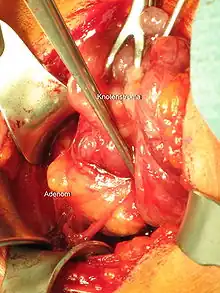

Parathyroïdectomie

La parathyroïdectomie est une ablation chirurgicale d'une ou plusieurs glandes parathyroïdes.